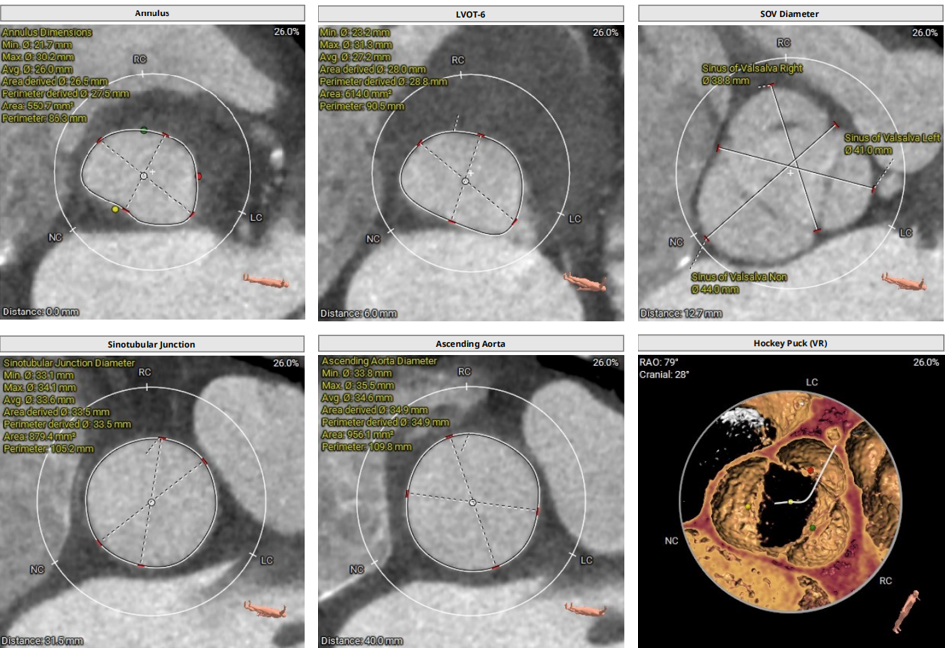

术前CT评估:

• Type1型二叶式主动脉瓣,R-N窦钙化融合嵴,瓣叶重度钙化伴增厚,L-N窦局部粘连。

• 冠脉开口高度可,左冠瓣叶稍冗长,左冠切线位瓣叶长度>冠脉开口到瓣叶附着缘距离,右冠切线位瓣叶长度<冠脉开口到瓣叶附着缘距离。

• 瓦氏窦、窦管交界内径可,升主动脉扩张,左室腔内径增大。

• 瓣环水平夹角46° ,主动脉弓宽度、角度尚可。

主动脉根部测量

冠脉阻挡风险评估